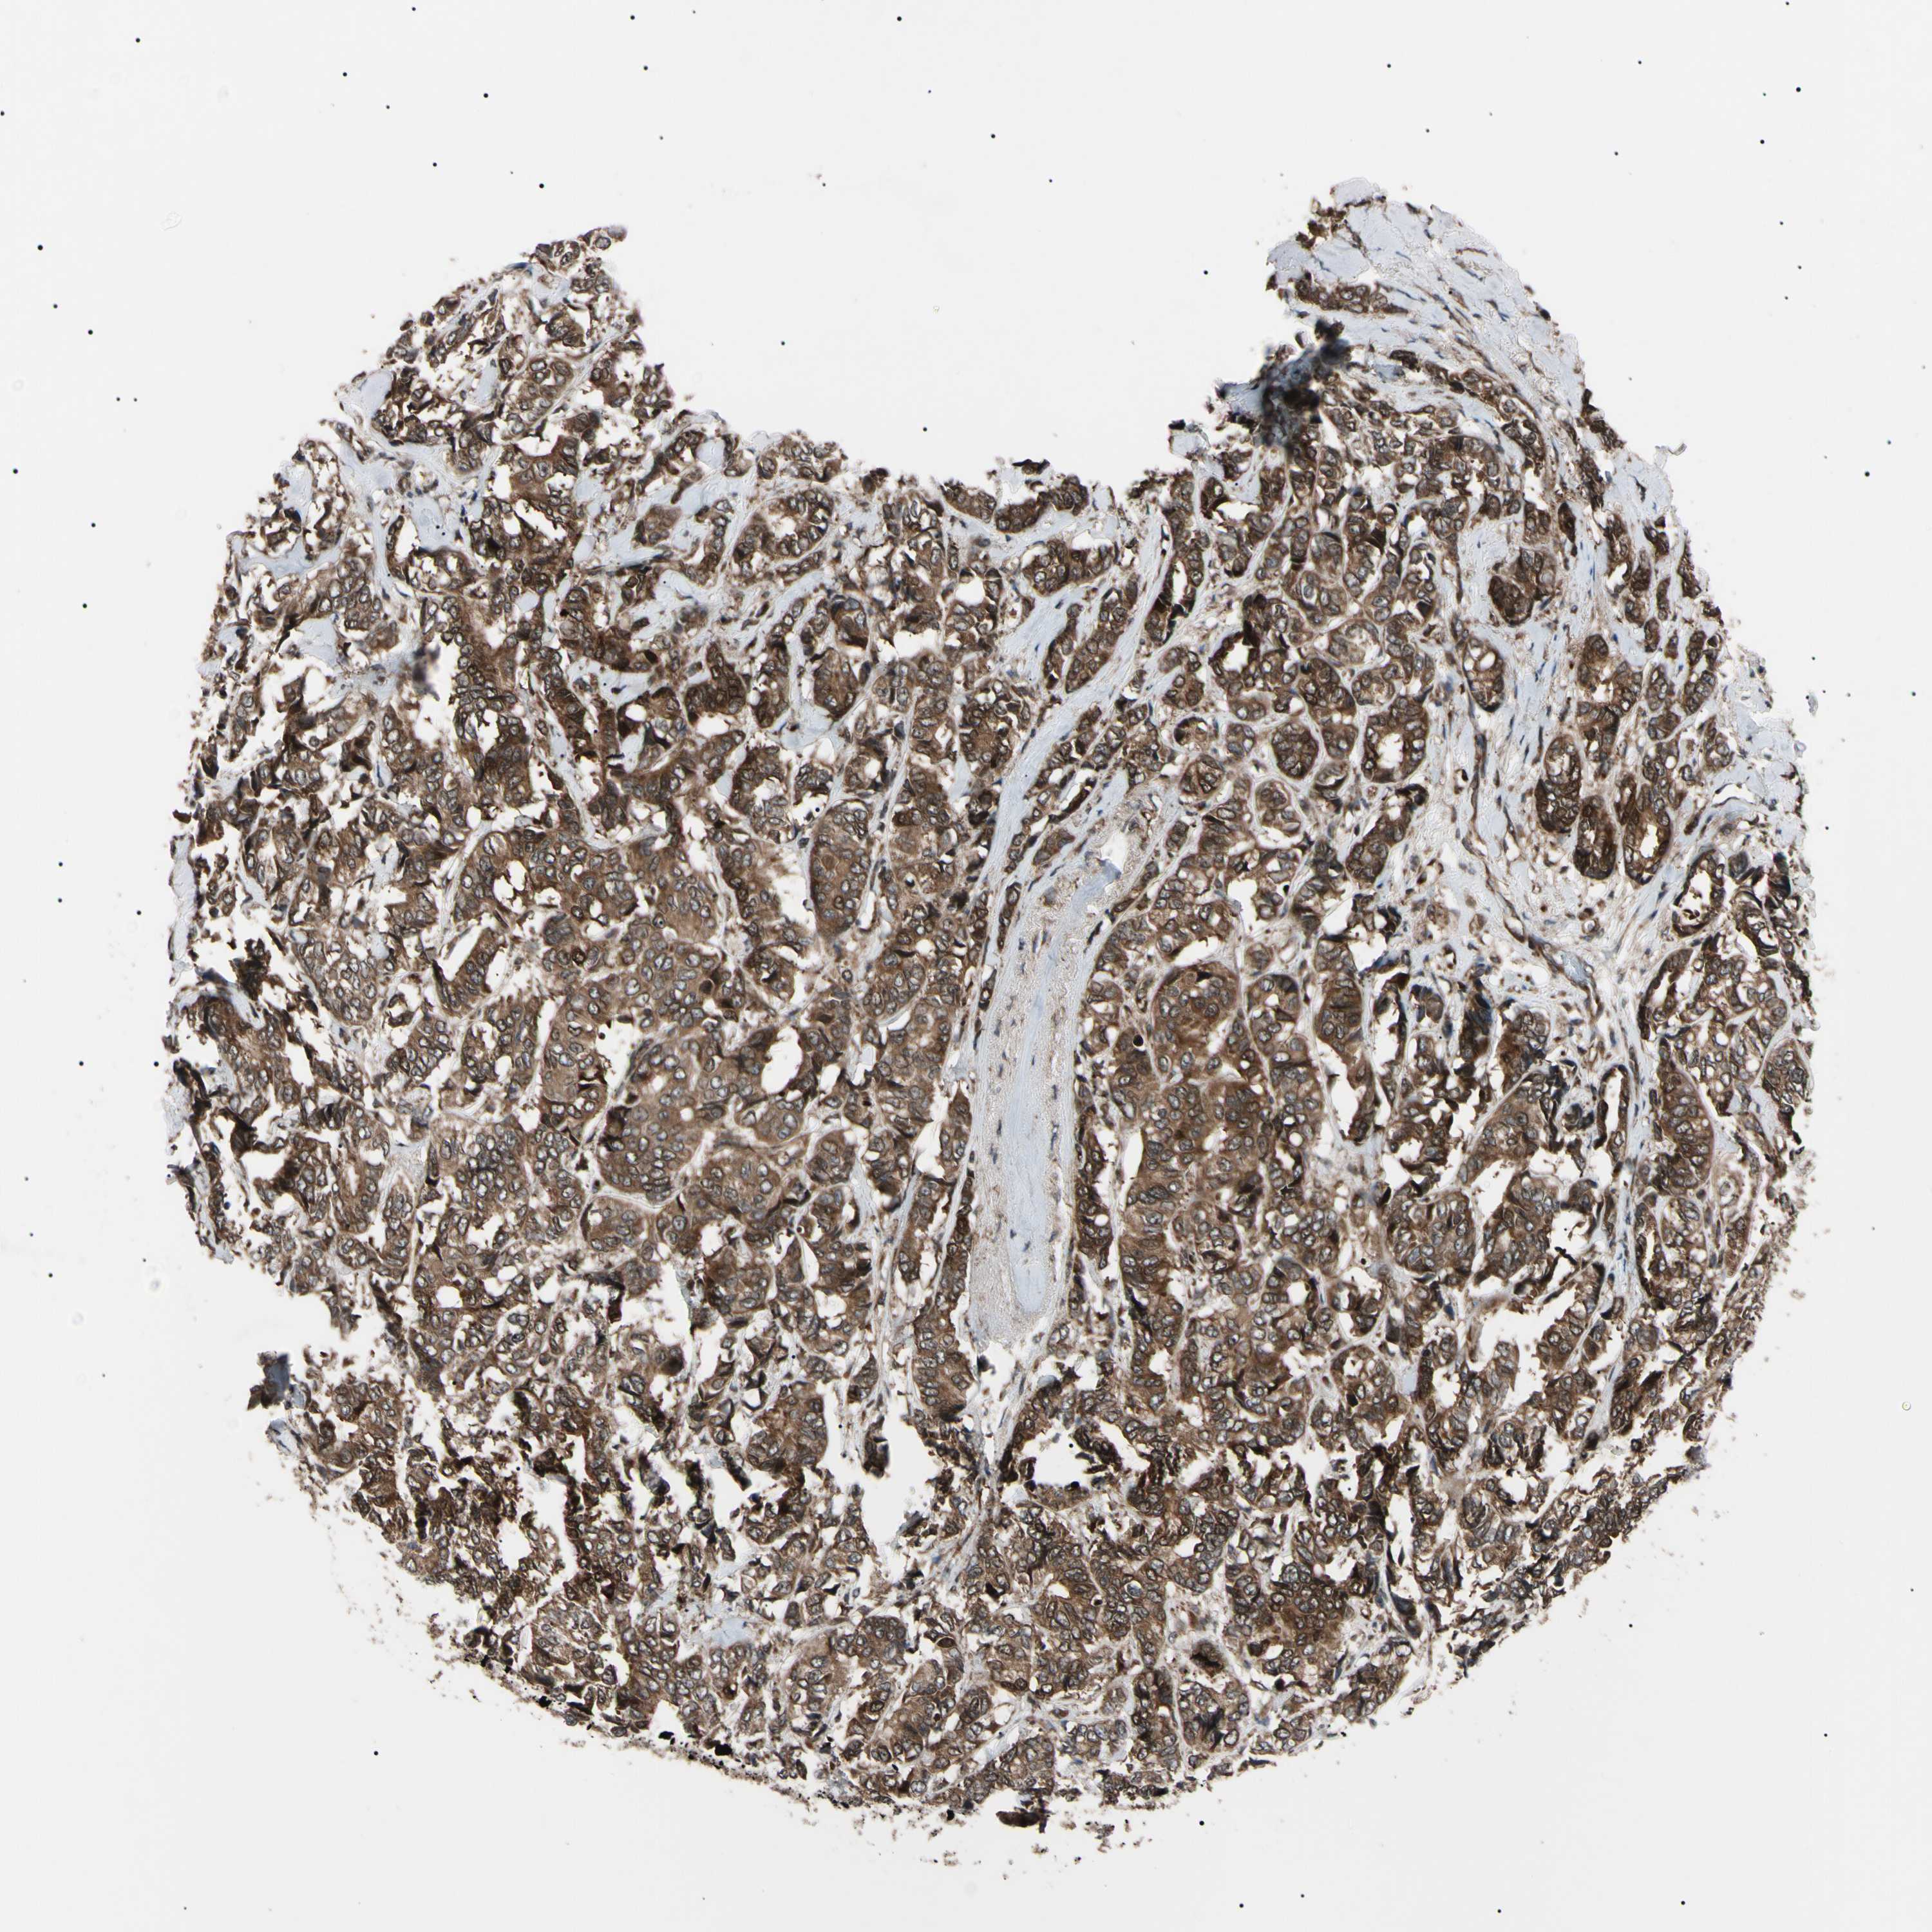

BRCA TCGA BRCA VALIDATION PROTEIN EXPRESSION